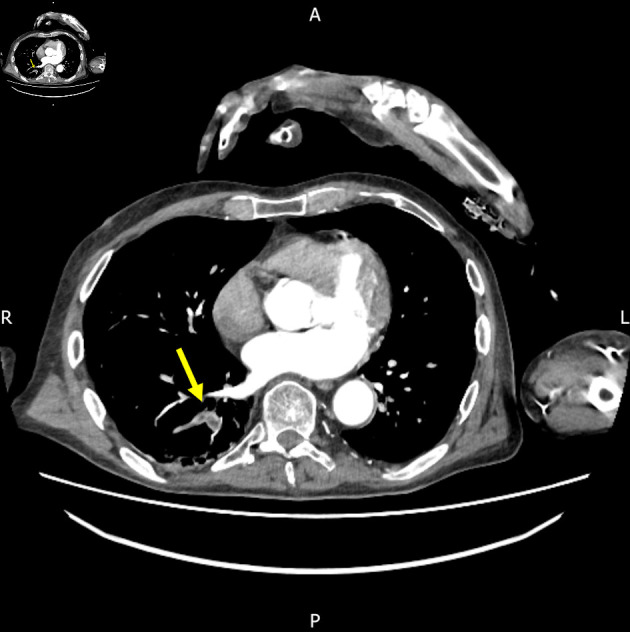

Abstract Image